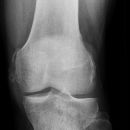

Kniegelenk

Tibiakopf